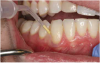

Clinical data were collected at the experimental site by one of two calibrated, blinded periodontists (RR or AK)9 and reported at baseline and 24 months. Data collection at one year has been described previously.9 During data collection, supragingival plaque was removed from the test and control teeth with a dental explorer; if any plaque deposit was visible on the explorer tip after the first pass across the tooth surface it was recorded as "positive." Following the recording of visible plaque, an absorbent paper strip (Periopaper, ProFLow; Amityville, NY, USA) was inserted into the experimental site sulcus for 30 seconds to collect the GCF sample. Strips contaminated with blood were discarded and a second sample was taken. The paper strip was placed into a coded sterile vial and frozen at -800 C. Gingival recession was then measured at the test and control sites using a University of North Carolina (UNC) 15 probe (Hu-Friedy; Chicago, IL, USA). Probing pocket depths (PD) were then measured at the same site and clinical attachment level (CAL) was calculated. BOP was recorded as positive for sites that bled within 30 seconds. Full-mouth pocket measurements and periodontal maintenance therapy were then completed by the dental student assigned to the case. At the end of the periodontal maintenance therapy appointment, a licensed dental hygienist (JH) performed SRP at the experimental sites and inserted 1 mg of MM into the test site pockets. (Figure 2) Participants returned for 6-month, 12-month, 18-month, and 24-month periodontal maintenance appointments. Because longer recall intervals may increase periodontitis risk,10 the intervals were extended to six months to determine if MM provided more periodontal stability compared as compared to repeated SRP alone in moderate periodontitis patients. At each maintenance appointment, scaling of shallow sites (≤ 4 mm) plus root planing of sites ≥ 5 mm was provided. Saliva collection was accomplished at the 24-month appointment, using a variation of the technique described by Navazesh.11 Patients rinsed with water and expectorated into a sterile collecting tube for five minutes while in a seated position. Saliva samples then were centrifuged at 2,000 RPM for 5 minutes and the supernatant was pipetted into coded sterile vials. Vials were then frozen at -800 C before further testing. Salivary sampling was a protocol change added after the initial informed consent; therefore, all of the subjects re-consented at the beginning of the 24-month appointment.

Figure 2. Application of MM into test site

Figure 2